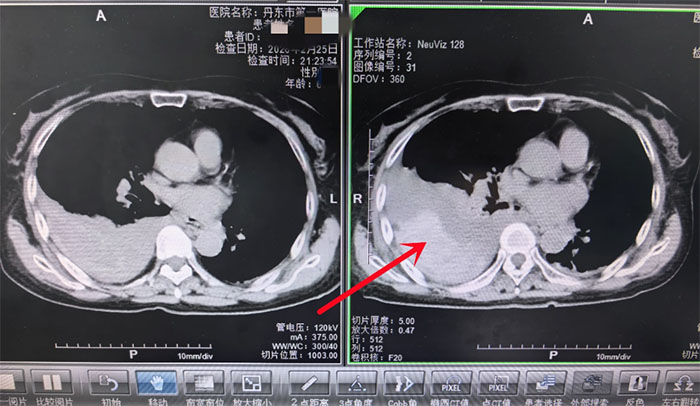

病情紧急,刘阿姨被火速收入胸外科接受进一步治疗。然而,实际病情比预想的还要糟糕。刘阿姨仅仅入院12小时后,再次复查CT显示:胸腔内的积血非但没有停止,反而迅速增多并形成了大血块——这是典型的“活动性出血”信号,意味着刘阿姨随时都可能陷入失血性休克。

(胸腔积液量明显增多)

(箭头所指为血凝块) 时间就是生命!我院胸外科副主任李林当机立断,带领科室医疗团队立即进行急诊手术治疗。